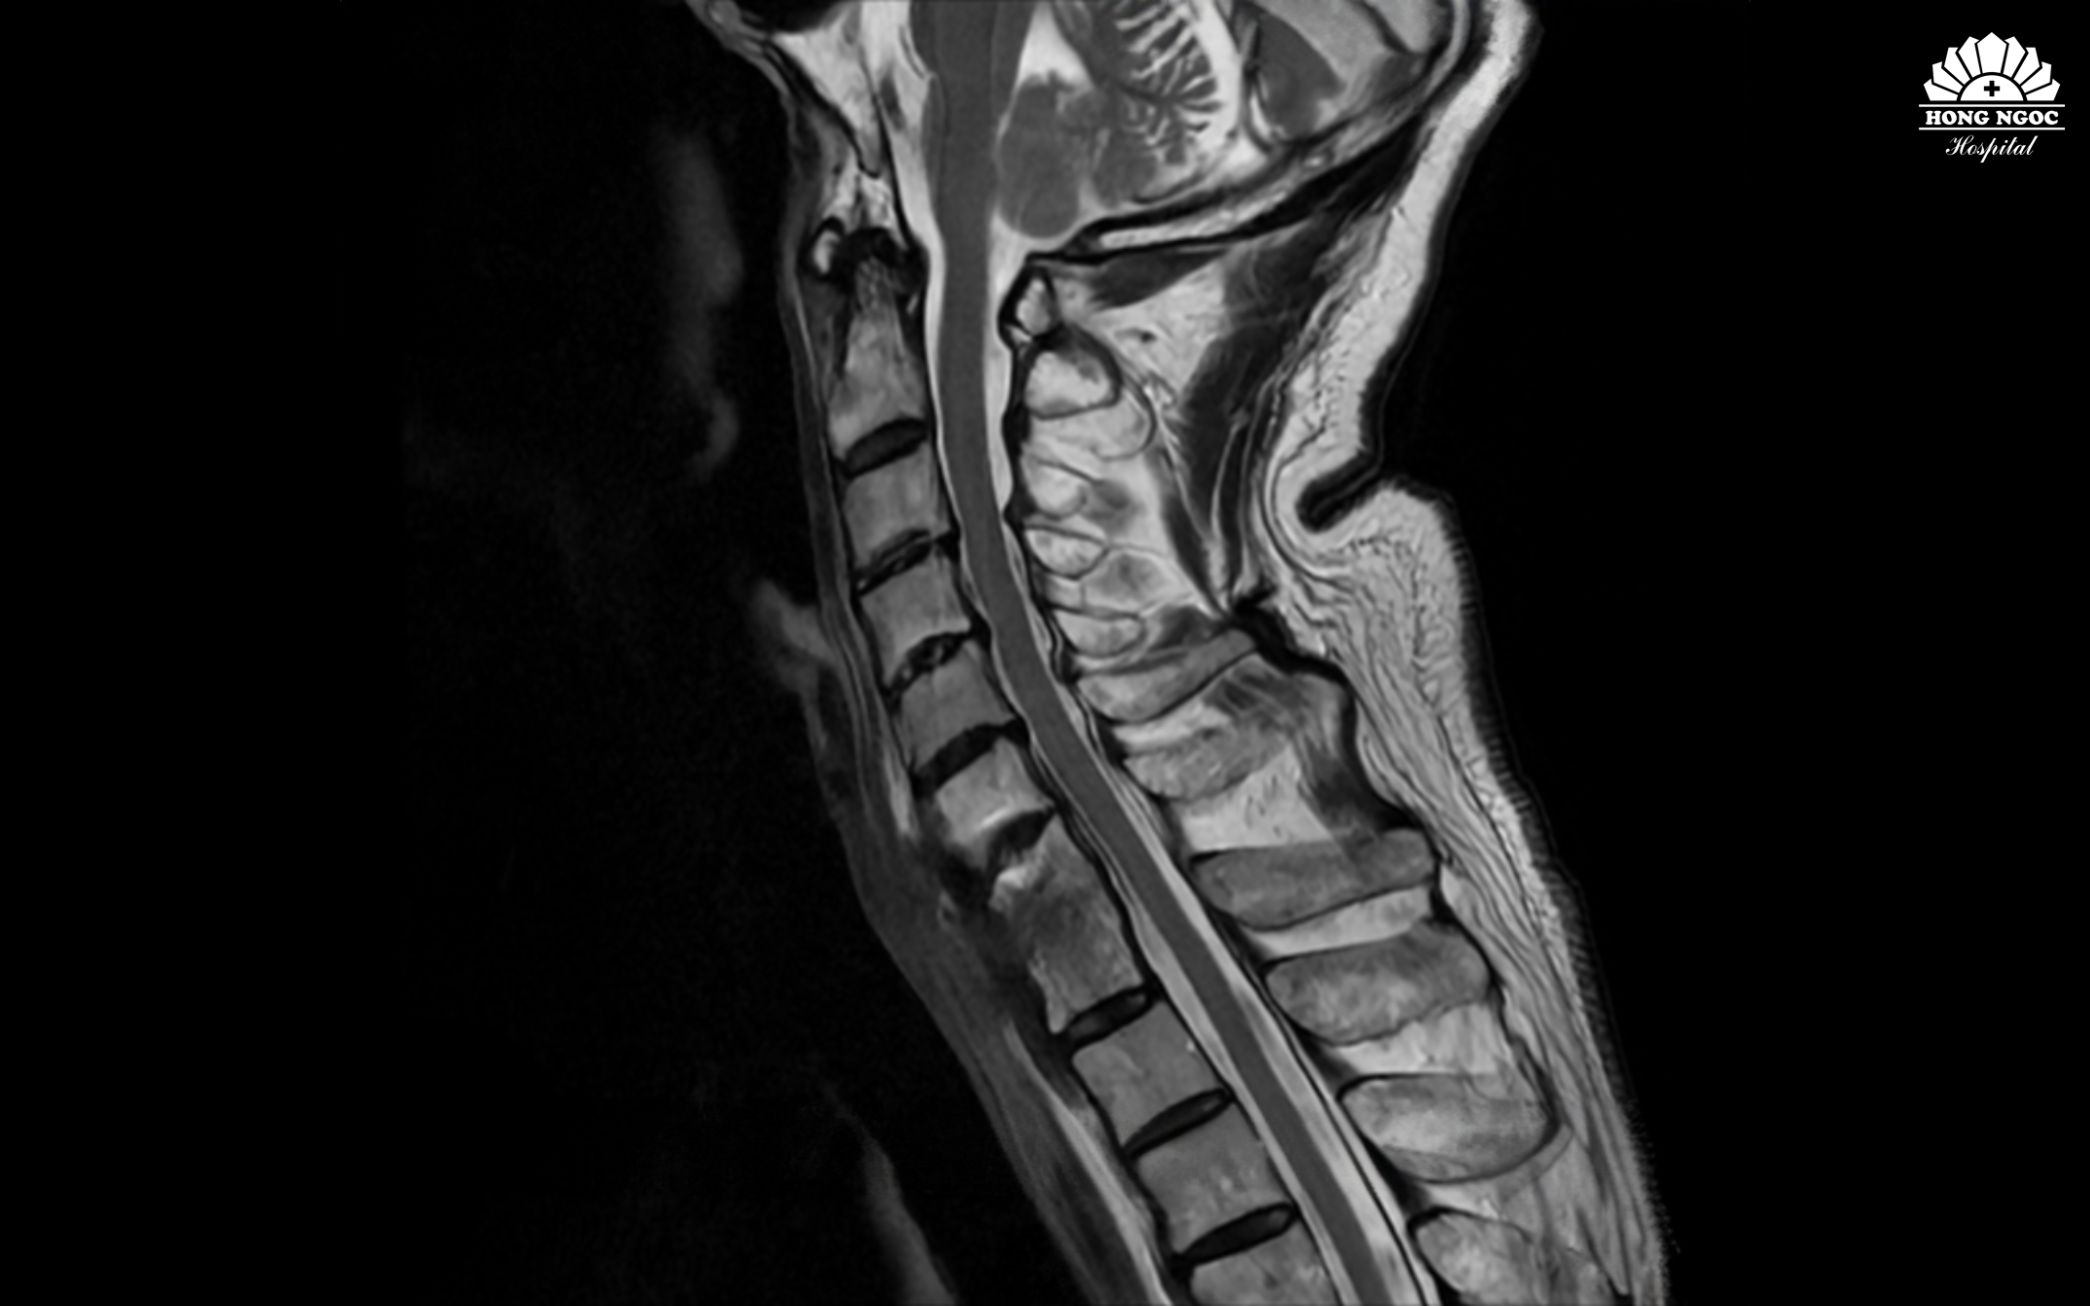

섬유 띠와 염증 부위를 제거하여 정상적인 생리적 곡선을 회복하고 경추를 안정화시켰습니다.

인공지능(AI)이 탑재된 3D C-arm 장비의 지원 아래 2시간여의 수술이 진행되었습니다. 하낌쭝 준교수와 응우옌꽝쭝 석사를 비롯한 의료진은 성공적으로 유착된 섬유 조직을 박리하고, 염증 부위를 치료하며 경추(목뼈)를 안정화시켰습니다. 수술 후 환자는 의식이 명료했으며, 목의 저림과 통증이 현저히 개선되었습니다. 사지 마비 증세는 없었고, 목을 부드럽게 돌리거나 젖히는 것이 가능했습니다.